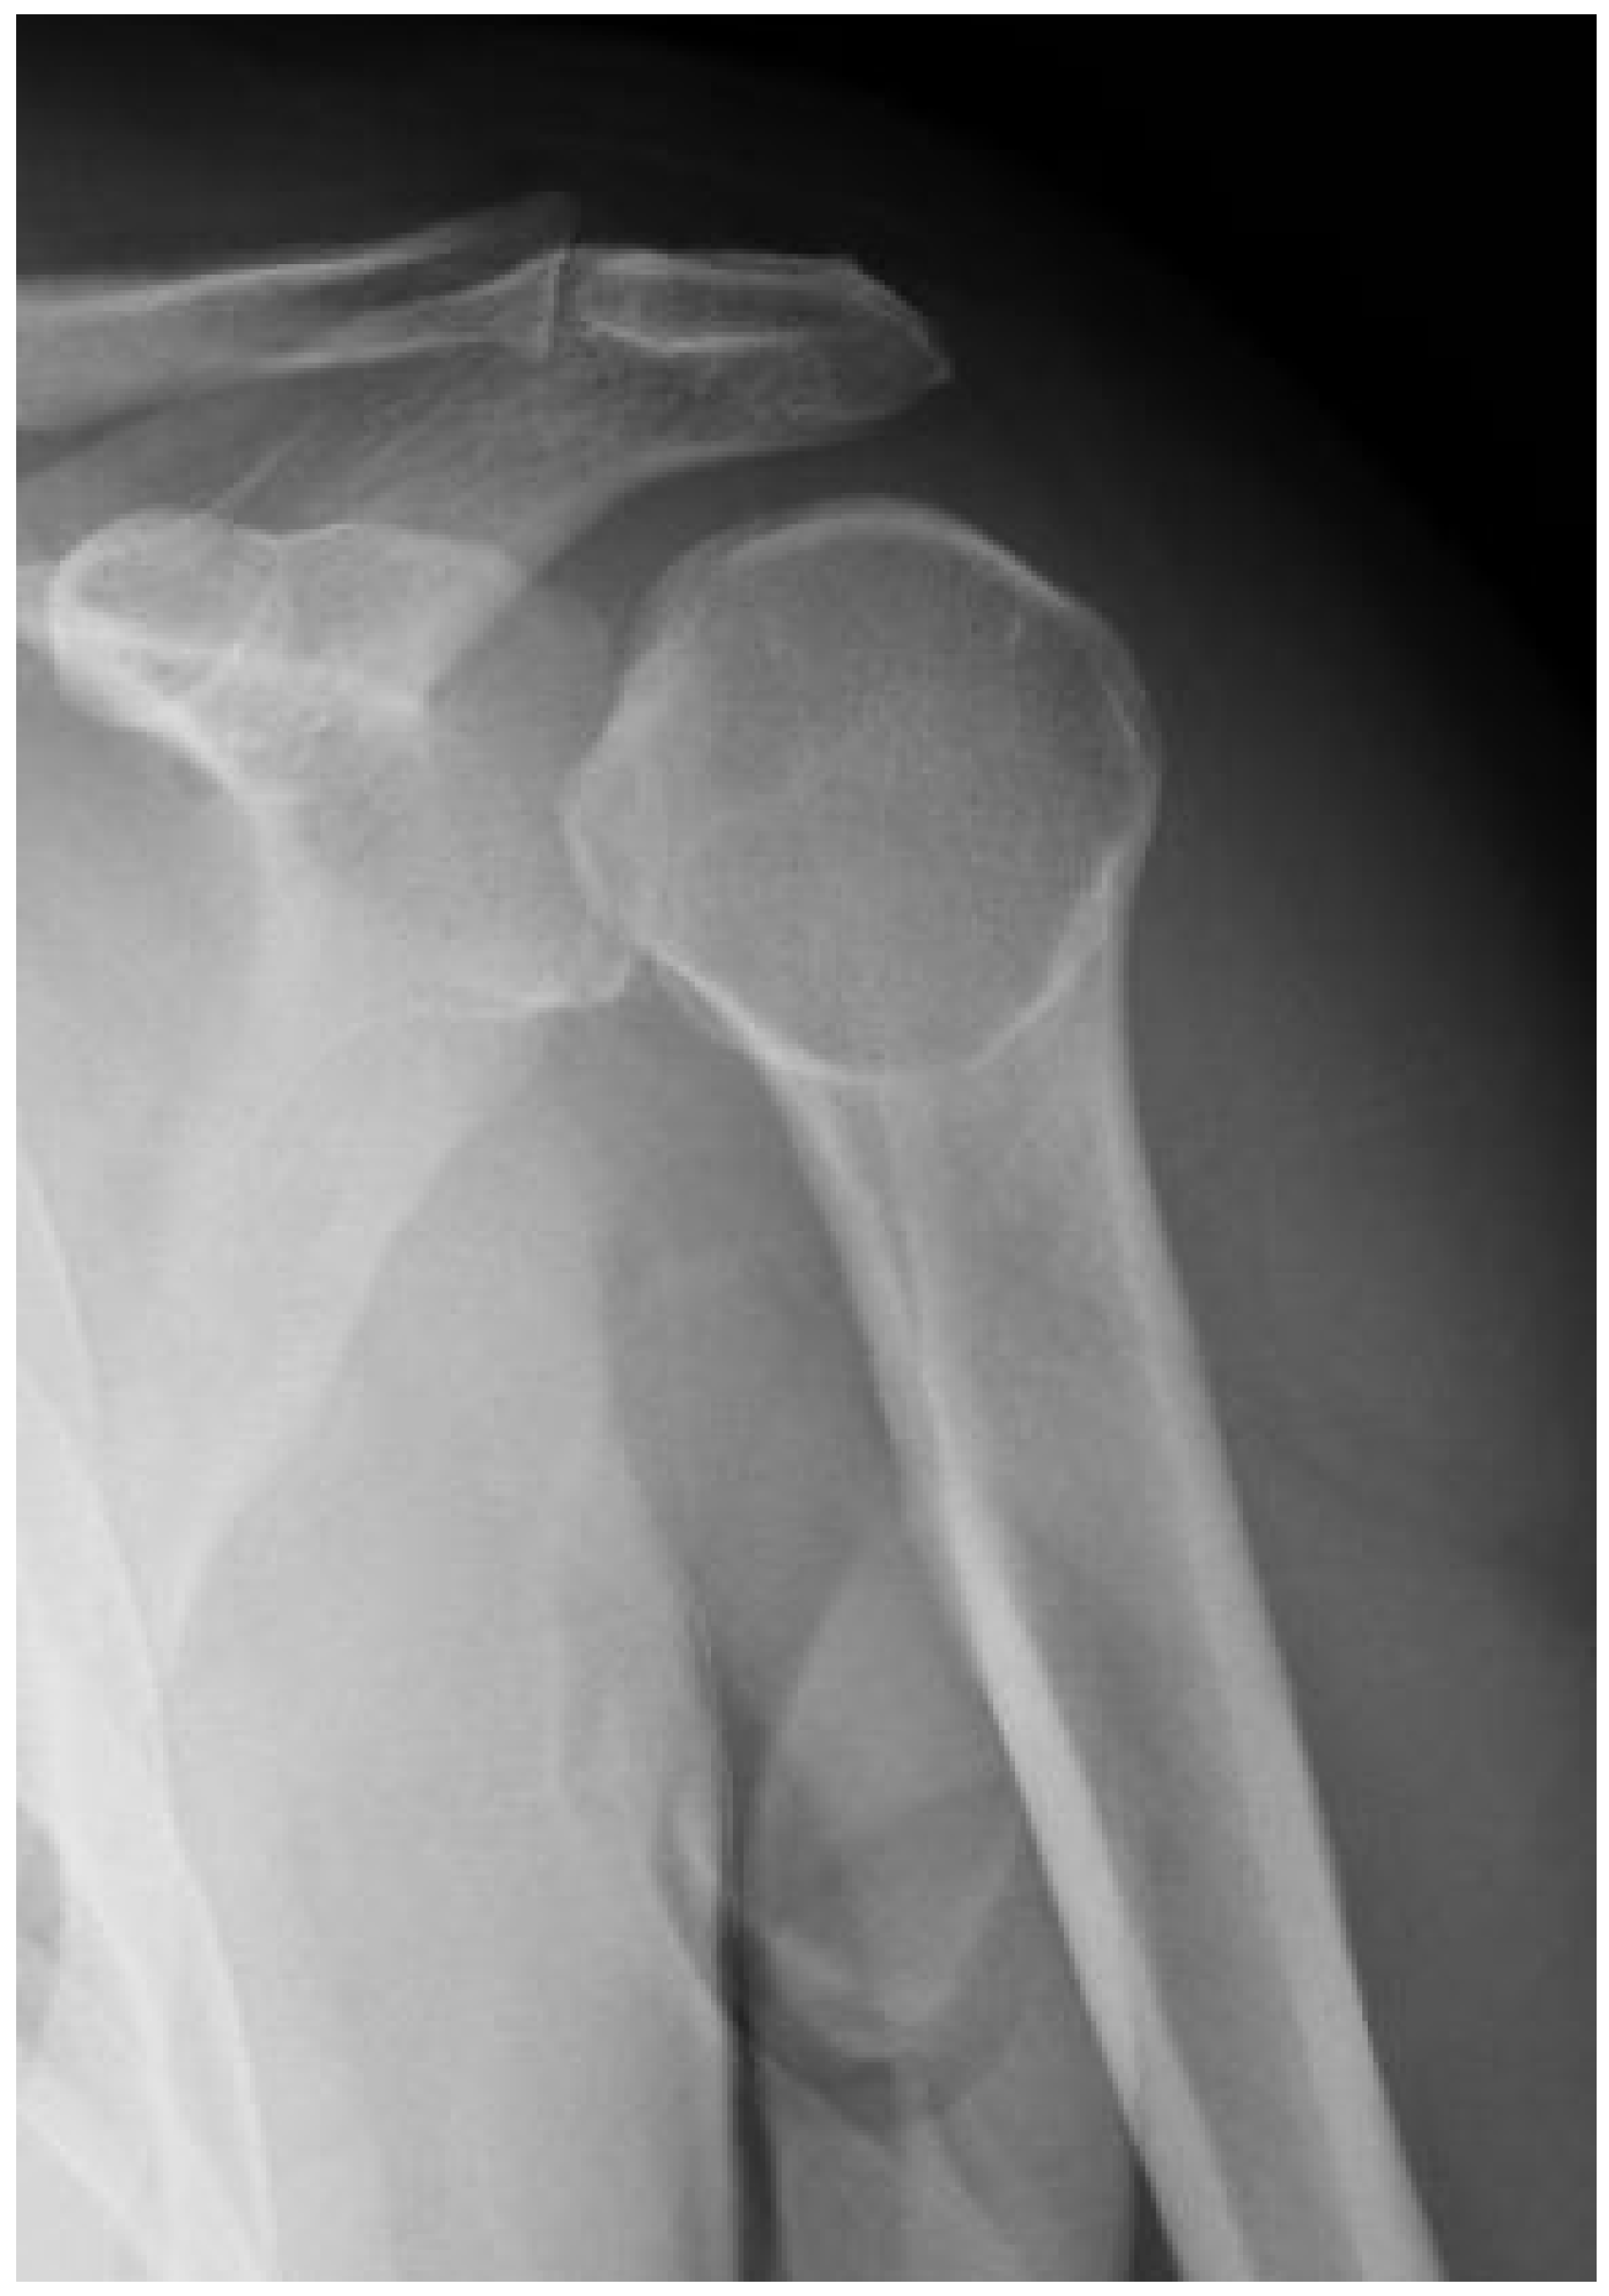

| 1 CP | M–49 | 19 days | 22 days | Hill–Sachs reverse lesion <50% | McLaughlin technique Subscapularis tendon transfer |

| 2 DF | F–49 | 70 days | 106 days | Hill–Sachs reverse lesion <50% | Subscapularis tendon transfer |

| 3 AA | M–54 | 6 days | 14 days | Hill–Sachs reverse lesion <50%, humeral insertional detachment of ST and LHB | Subscapularis tendon transfer |

| 4 CI | M–34 | 2 days | 9 days | Hill–Sachs reverse lesion <50% | Repair through a plication of subscapularis tendon (McLaughlin modified technique) |